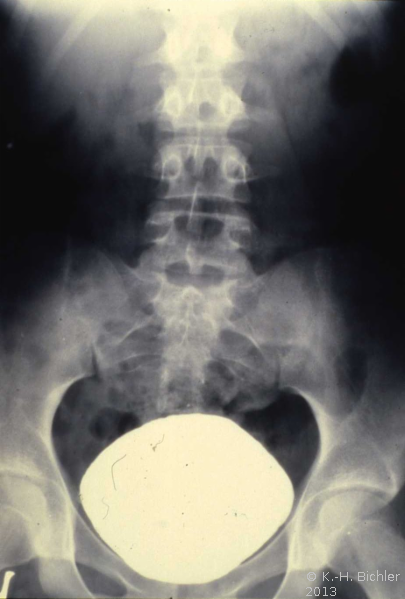

Die Röntgenübersicht der Niere und ableitenden Harnwege zeigten keinen Anhalt für Konkrement. Im Ausscheidungsurogramm eine "stumme Niere" links (Abbildung 19a). Bei der retrograden Sondierung links fand sich keine Abflussbehinderung (Stein oder Stenose) (Abbildung 19c). Im MCU kein Anhalt für Reflux (Abbildung 19b). Im Nierenfunktionsszintigramm MAG3 wurde eine seitengetrennte Funktionsverteilung von rechts zu links wie 93% zu 7% festgestellt. Zur Abklärung eventueller Gefäßalterationen erfolgte eine Renovasographie mit dem Nachweis einer langstreckigen Stenose der linken Arteria renalis (Abbildung 19d). Wegen des Verdachtes auf eine generalisierte Arteriitis wurden Angiographien weiterer Gefäßgebiete durchgeführt: Dabei fanden sich eine geringgradige Einengung der infrarenalen Aorta und der linken Arteria subclavia.